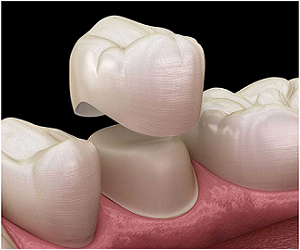

General Dentistry

General dentists provide services related to the general maintenance of oral hygiene and tooth health